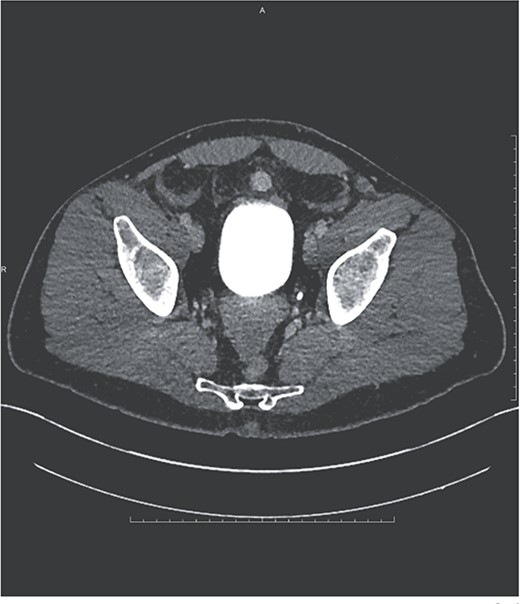

Additional findings included hemorrhagic fluid in the pelvis, right paracolic gutter, and surrounding the right hepatic lobe as well as a small hyper-enhancing mass adjacent to the bladder (see Fig. 2).

Ovoid hyperenhancing lesion anterior to the dome of the bladder, representing an additional area of splenosis.